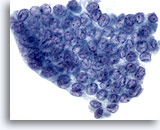

Zeer waarschijnlijk benigne

In deze categorie vallen die folliculaire laesies die een macrofolliculair of gemengd micro- en macrofolliculair patroon vertonen met weinig tot overvloedig colloïde op de achtergrond. Op ThinPrep zijn macrofollikels te zien als lagen van tientallen gelijkmatig verdeelde folliculaire cellen met een goede afstand tussen kernen. De significantie van losse folliculaire cellen op ThinPrep in onzeker, omdat deze worden waargenomen in een verder micro- of macrofolliculair patroon. Omdat de waarschijnlijkheid dat deze laesies maligniteit vertonen (folliculaire variant van papillair carcinoom of folliculair carcinoom) bij histologie laag is, maar niet helemaal nul (in de literatuur varieert het percentage van 0 tot 43%) [6, 9, 12, 13, 14, 15, 16, 17, 18, 19, 20, 21, 24, 25, 26, 27] waarbij op drie na[14, 16, 27] alle studies minder dan 6% rapporteerden, noemen we dit daarom zeer waarschijnlijk benigne in plaats van onmiskenbaar benigne.